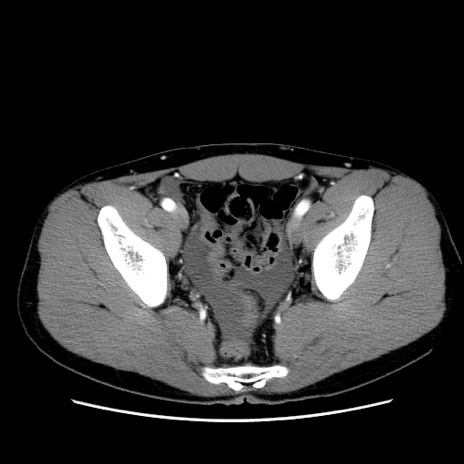

冠状断像

症例36(横断像)

【症例】20歳代 男性

【主訴】心窩部痛

【現病歴】今朝より上腹部痛あり。一旦軽快していたが再度出現したため救急要請。昨日夕に白身の魚を含む刺身を食べた。

【身体所見】BP 136/89mmHg、HR 74/min、BT 37.0℃、腹部:膨満、軟、心窩部に圧痛あり。反跳痛なし、筋性防御なし、腸雑音やや亢進あり。

【データ】WBC 17700、CRP 0.48